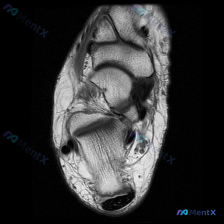

刚整理了一份膝关节MRI读片病例,分享出来和大家一起讨论一下思路。 病例基本影像信息 这是一张膝关节MRI(T2序列)轴位图像,层面覆盖膝关节前部,包含髌骨、股骨滑车及周围软组织结构: - 髌骨:骨皮质信号缺失(低信号),髓腔信号正常,皮质连续性尚可,无明显骨折线 - 股骨滑车:位于髌骨后方,可见内...

今天看到一份很有警示意义的膝关节MRI读片病例,整理出来和大家分享一下。这是一份经过髌股关节区域的膝关节轴位T2加权MRI,原始问题提示观察「软骨异常」,我们先把影像所见整理清楚: 一、病例基本影像信息 1. 髌股关节区域:髌骨前方及关节周围软组织可见弥漫性高信号,符合水肿/炎性渗出表现;髌股关节外...

看到一份很有启发的膝关节MRI病例,初始提示是「半月板异常」,但读片后的发现和一开始的方向完全不一样,整理一下完整分析思路跟大家分享。 一、病例影像基础信息 这是膝关节MRI矢状位T2加权图像,我们先整理所有客观发现: 1. 骨骼关节:股骨远端、胫骨近端、髌骨骨皮质完整,无明显骨折或骨质破坏,髌骨与...